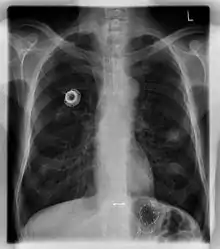

The port is usually inserted in the upper chest (known as a "chest port"), just below the clavicle or collar bone, with the catheter inserted into the jugular vein.

A port consists of a reservoir compartment (the portal) that has a silicone bubble for needle insertion (the septum), with an attached plastic tube (the catheter). The device is surgically inserted under the skin in the upper chest or in the arm and appears as a bump under the skin. It requires no special maintenance other than occasional flushing to keep clear. It is completely internal so swimming and bathing are not a problem. The catheter runs from the portal and is surgically inserted into a vein (usually the jugular vein or less optimally the subclavian vein). Ideally, the catheter terminates in the superior vena cava or the right atrium. This position allows infused agents to be spread throughout the body quickly and efficiently.

The port is then sutured on two sites to the underlying muscles. The tip of the catheter is checked for kinks and position using a fluoroscope. Besides that, aspiration of blood and contrast injection through the chemoport can also be used to confirm the position. The port is the closed in two layers (subcutaneous tissue is sutured first, followed by the skin). Sterile dressing is then placed on the port.[3] The optimum site to park the tip of the catheter is at the cavo-atrial junction or with margin of error of not more than 4 cm above the junction.[3]

A follow-up on a chest radiograph can immediately detect complications associated with the procedure such as pneumothorax, hemothorax and malpositions of the catheter. However, routine chest radiography is not needed due to the low complication rates associated with the procedure. The chest radiograph is only done if there is clinical suspicion of a complication.[4]